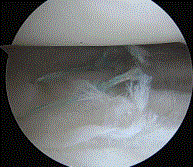

传统手术治疗半月板放射状撕裂,创伤大、副损伤多,显然不适合正处于黄金年龄的小李。针对小李的情况,骨外一科运动医学团队为他制定了膝关节镜下微创治疗的手术方案——仅在膝盖周围开两个0.5厘米大小的微小切口,医生通过高清内镜精准定位撕裂部位,再使用专用的缝合器械将撕裂的半月板牢牢“缝合”。整个手术耗时约40分钟,术中出血量不足10毫升。术后第二天,小李就能在支具辅助的保护下扶拐行走;术后一周,小李的膝盖疼痛明显缓解,可以做基本的屈伸活动。目前,小李正在骨外一科运动医学团队的指导下,有条不紊地开展肢体功能康复锻炼,为回归日常生活积蓄力量。